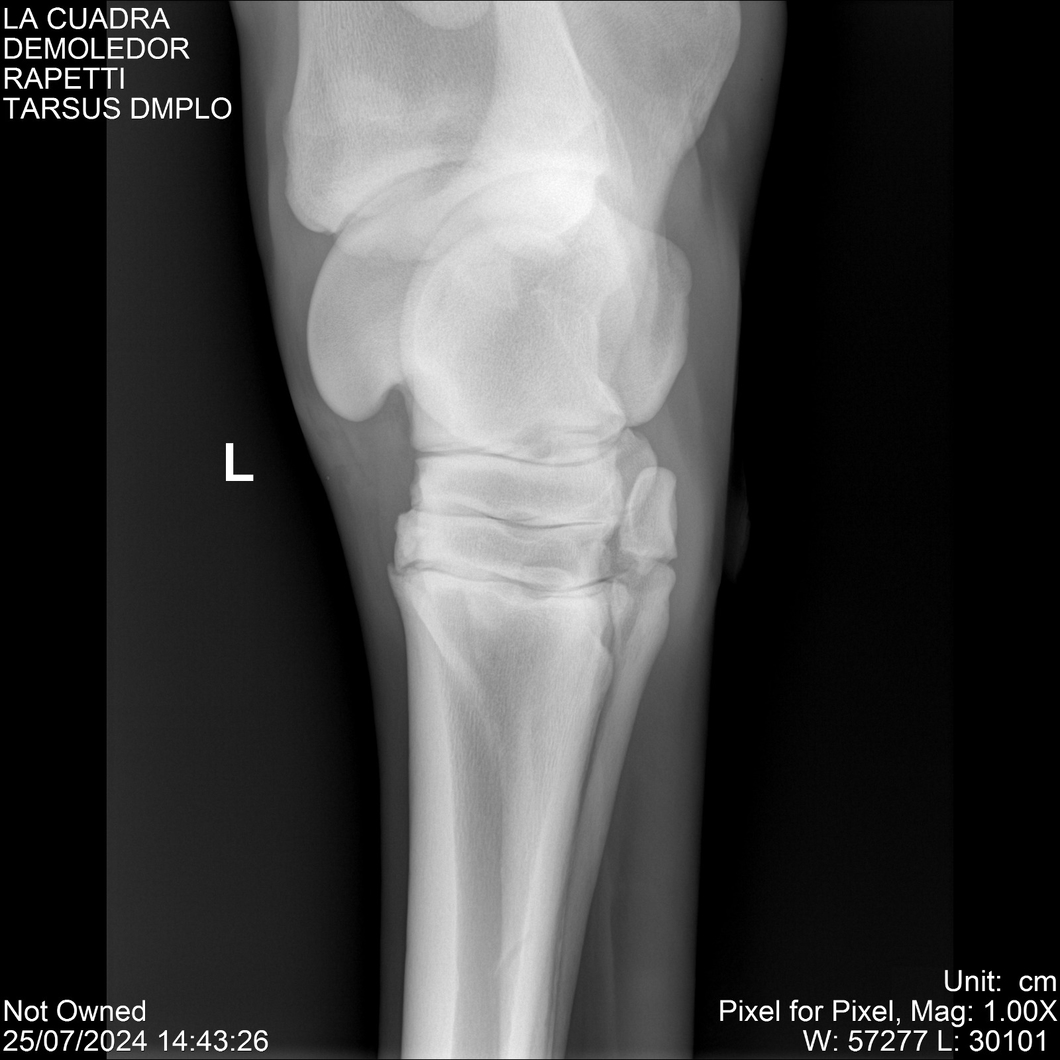

LOTE 14, DEMOLEDOR 🔥 🔥 🔥 Lote Anterior Volver al remate Lote Siguiente Ficha Contacto Montevideo - Ficha del Lote Identificador: #284454 Categoría: Yeguarizos Montevideo - 89 Visualizaciones ClicData Contacto Empresa: Abelenda N. R., Walter Hugo Nombre*: Teléfono* : E-mail* : Mensaje Enviar Registrese gratis Este contenido Exclusivo está disponible sólo para usuarios registrados Ingresar